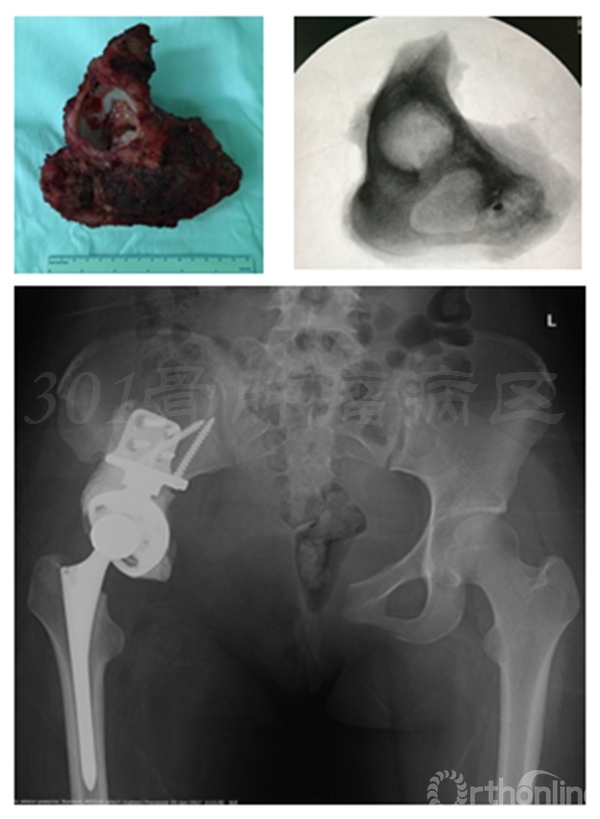

患者女性,术前X片提示:左侧骨盆Ⅱ+Ⅲ区溶骨性改变,诊断考虑骨巨细胞瘤合并动脉瘤样骨囊肿。血管栓塞后行骨盆Ⅱ+Ⅲ区切除,股骨头旷置术。术后病理报告是骨巨细胞瘤恶变,故行化疗6个月。术后13年随访,患者有跛行,但行走自如。

术前X线片

血管栓塞

股骨头旷置术

术后13年X线片